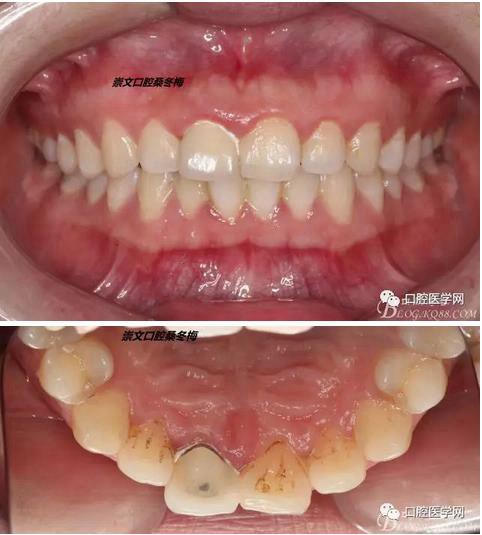

牙冠延長術(shù)后6周復(fù)診牙齦齦緣形態(tài)恢復(fù)良好,齦乳頭有些欠缺,患者著急永久修復(fù)。

比色

纖維樁+樹脂核

樁道長14mm

備牙

戴牙